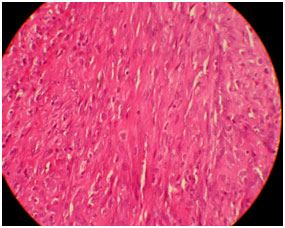

On microscopic examination, there were cavernous vascular spaces, solid spindle cells attached to vessel walls and vacuolated epitheloidendothelial cells [Table/Fig-5,6]. The lesion was well circumscribed, highly cellular with vascular proliferation and slit like spaces [Table/Fig-5,7]. There were few lymphocytes and eosinophils. Larger thin walled vessels with RBCs and areas of hemorrhage were also appreciated. The lesion did not show any cellular atypia and was well circumscribed without infiltration to surrounding structures. Histopathological diagnosis of vascular lesion i.e., spindle cell haemangioma was given. Immunohistochemistry (IHC) was done for the markers CD- 34 and CD- 31 for evaluation of origin of these spindle cells which were triple positive. Pericytes with surrounding blood vessels, split like vascular spaces lined by endothelial cells were positive for CD-34 and cells in vascular channels near endothelial lining were positive for CD 31 [Table/Fig-8] [1].

H&E (10X) Histopathology slide showing spindle to epitheloid endothelial cells with slit like spaces within proliferations